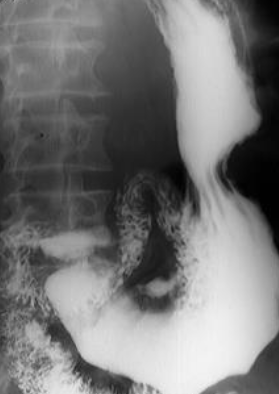

Neoplasm malign gastric vegetant